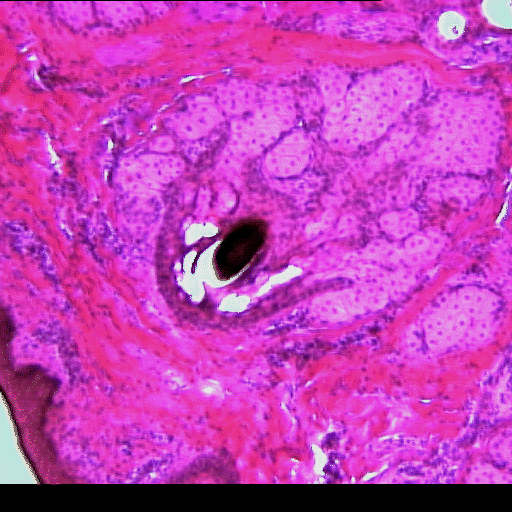

(EN) : Close-up view of a cross section of an eyelid (Hematoxylin and eosin stain (H&E), x40): Accessory structure of the eye.

(FR) : Vue rapprochée d'une coupe transversale d'une paupière (coloration à l'hématoxyline et à l'éosine (H&E), x40): Structure accessoire de l'oeil.